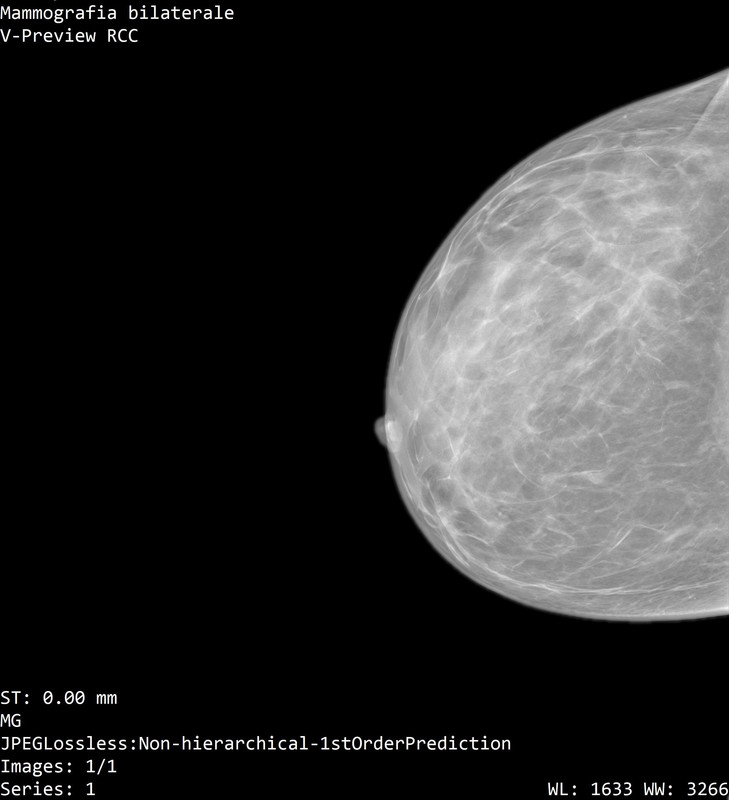

Onestamente non capisco neppure quale sia la mammella destra dalla sinistra...

Il referto dice:

"a dx al passaggio tra i quadranti inferiori e' meglio visibile un focolaio di microcalcificazioni, non riconoscibile con certezza all'ecografia mirata, meritevole di caratterizzazione mediante agobiopsia con sistema VAB sotto guida mammografica